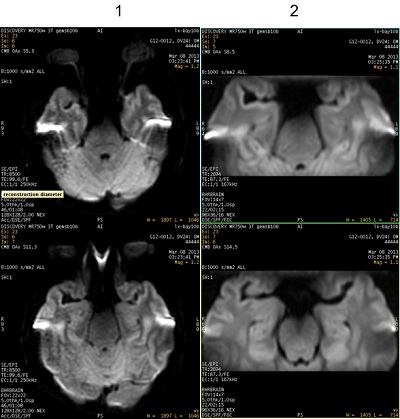

| Number | Description |

|---|---|

| 1 | DWI images acquired with Excitation Mode: Selective. Note the increased images magnetic susceptibility distortion effect. |

| 2 | DWI images acquired with Excitation Mode: Focus. Note the increased resolution due to less magnetic susceptibility distortion effect. |